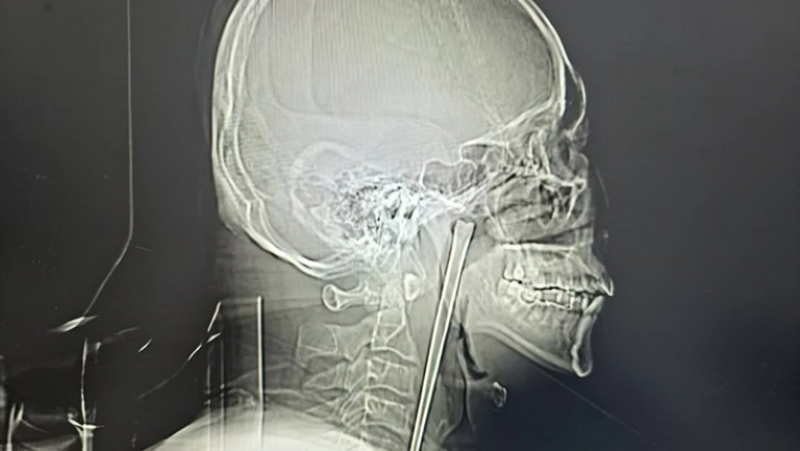

سجلت الصين حالة طبية نادرة لرجل ظل يعاني لسنوات من جسم معدني عالق في حلقه، قبل أن يتمكن الأطباء من إزالته بنجاح.

عاش رجل صيني لمدة 8 سنوات بوجود عود معدني طويل عالق في حلقه، قبل أن يتمكن الأطباء أخيرًا من إزالته بنجاح داخل أحد المستشفيات الصينية في مدينة داليان، وذلك وفقًا لما نشره Oddity Central.

وبحسب ما أعلنه مستشفى داليان المركزي، فإن الرجل البالغ من العمر 46 عامًا توجّه مؤخرًا إلى المستشفى وهو يعاني من آلام حادة في الحلق وشعور مستمر بوجود جسم غريب، ما دفع الأطباء لإجراء فحوصات دقيقة كشفت مفاجأة.

وأظهرت الأشعة وجود جسم معدني بطول 12 سنتيمترًا عالق داخل حلق المريض، وعند سؤاله، أوضح أنه ابتلع هذا العود عن طريق الخطأ قبل نحو 8 سنوات أثناء تناول الطعام، دون أن يتخذ أي إجراء طبي جاد في ذلك الوقت.

وقرر الفريق الطبي إجراء جراحة دقيقة طفيفة التوغل عبر الفم، لتجنب شق الرقبة، وتمكنوا بالفعل من استخراج العود المعدني بالكامل دون مضاعفات تُذكر.